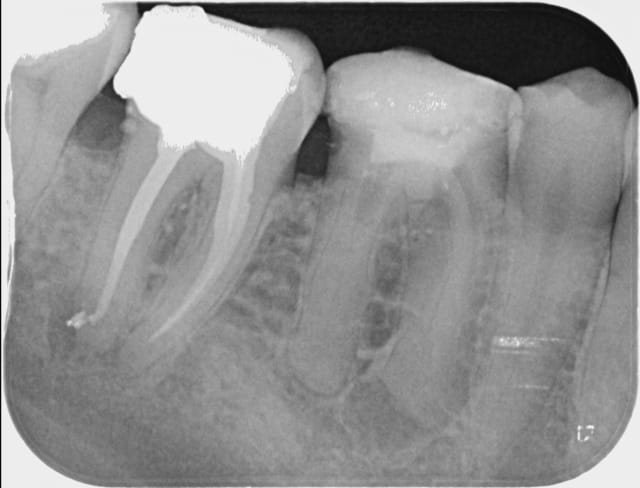

vu la pré op j'avais très peur du résultat mais avec des limes 10 puis 15 avec du glyde et beaucoup de patience, c'est passé! je suis pas mécontent du résultat sur ce truc qui sommeille depuis 40 ans

Bonjour , pourriez vous m'expliquer l'excès de produit au niveau de l'apex au niveau des racines obturées , c'est un dépassement ? Merci .

> Bonjour , pourriez vous m'expliquer l'excès de produit au niveau de l'apex au

> niveau des racines obturées , c'est un dépassement ? Merci .